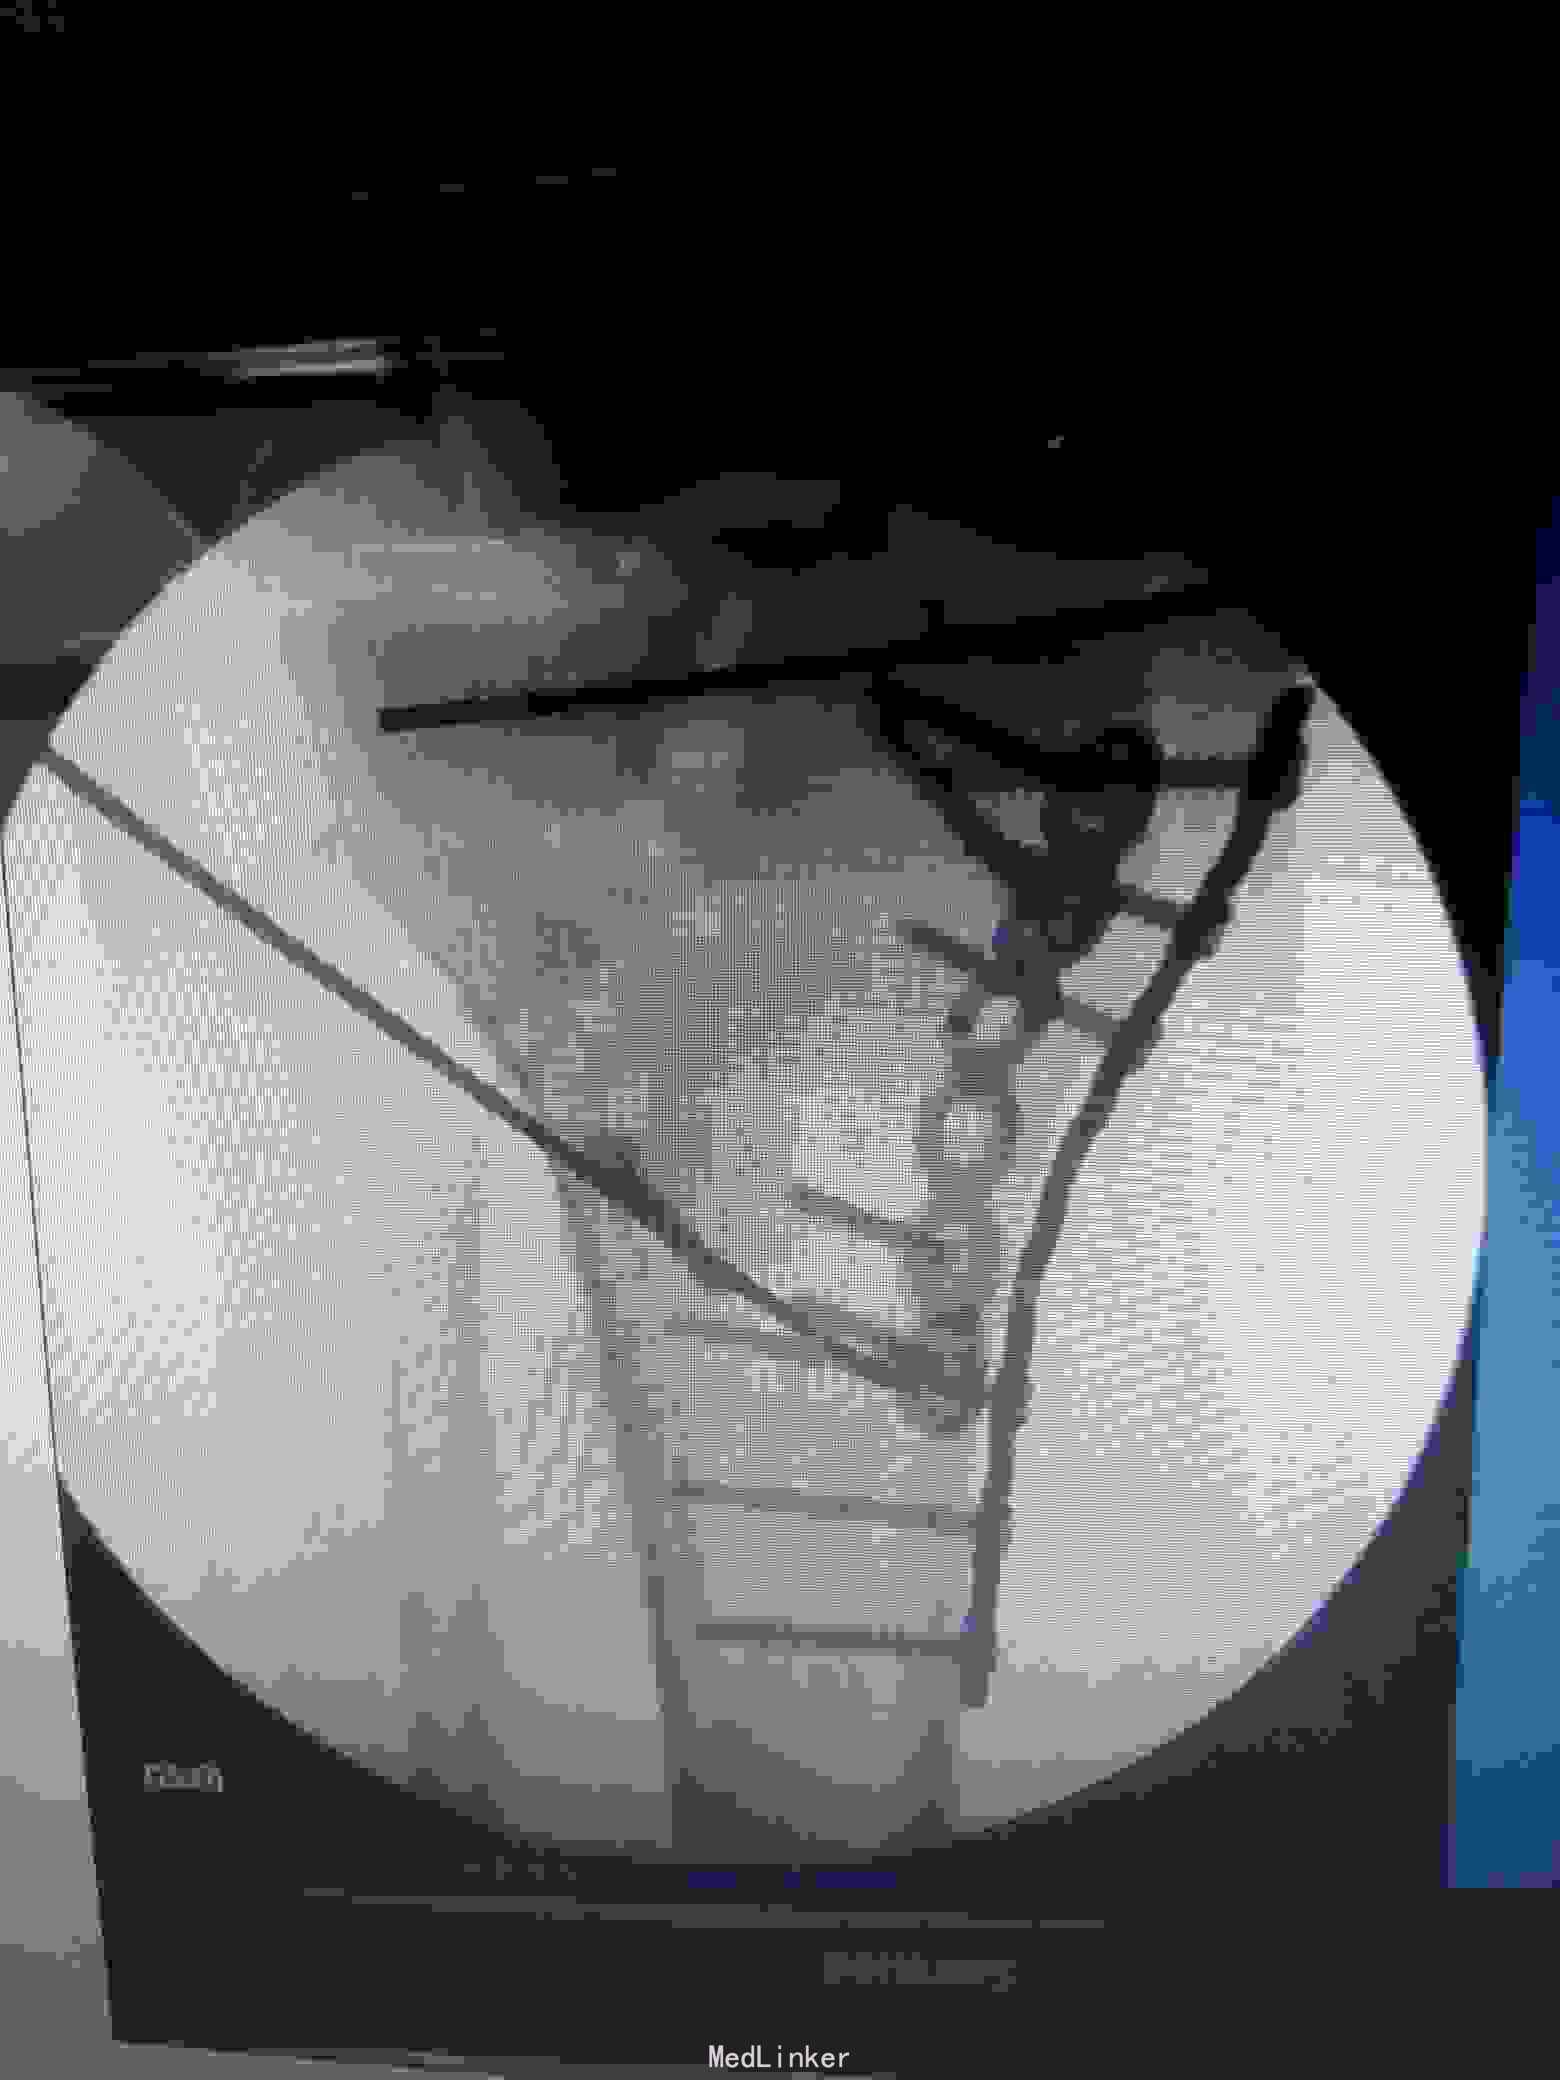

治疗:采用俯漂体位,先行俯卧,行后内侧入路,显露胫骨平台后内侧,可以清楚显露后内侧及内侧,可以同时固定后内侧及内侧骨块。然后再漂致仰卧位,行前外切口行前外侧的钢板固定。

术后复查X线片提示:骨折端对位对线好,力线平。

讨论:内外侧胫骨平台骨折,正常情况下只需在仰卧位下分别行内侧及前外侧入路进行内外侧柱的固定,但是如果骨折累计后内侧骨块,单纯内侧钢板固定仍无法稳定骨折端,这时候需要后内侧钢板的固定,仰卧位下无法清楚显露后内侧骨块,并进行固定,我们采用俯漂体位进行复位固定,俯卧下行后内侧入路,可以清楚显露后内侧及内侧骨块,同时可方便进行固定。